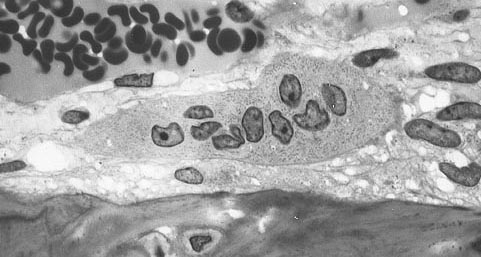

골다공증의 근본적인 기전은 뼈 흡수와 뼈 형성 사이의 불균형이다.[95][96] 정상적인 뼈에서는 뼈의 기질 리모델링이 지속적으로 일어난다. 모든 뼈 질량의 최대 10%가 어느 시점에서든 리모델링을 겪을 수 있는데, 이 과정은 1963년 프로스트(Frost)와 토마스(Thomas)가 처음 기술한 뼈 다세포 단위(BMU)에서 일어난다.[97] 파골 세포는 전사 인자 PU.1의 도움을 받아 뼈 기질을 분해하는 반면, 골아 세포는 뼈 기질을 재건한다. 파골 세포가 골아 세포가 뼈를 재건하는 것보다 더 빠르게 뼈 기질을 분해할 때 뼈 질량 밀도가 낮아질 수 있다.[95][98]

잔기둥 뼈 (또는 해면골)는 긴 뼈와 척추의 끝 부분에 있는 스펀지 같은 뼈이다. 피질 뼈는 뼈의 단단한 바깥쪽 껍질과 긴 뼈의 중앙 부분이다. 골아 세포와 파골 세포가 뼈 표면에 서식하기 때문에 잔기둥 뼈는 더 활동적이며 뼈 회전과 리모델링의 영향을 더 많이 받는다. 뼈 밀도가 감소할 뿐만 아니라 뼈의 미세 구조도 파괴된다. 잔기둥 뼈의 약한 스피큘이 부러지고("미세 균열") 더 약한 뼈로 대체된다. 일반적인 골다공증성 골절 부위인 손목, 엉덩이 및 척추는 피질 뼈에 대한 잔기둥 뼈의 비율이 상대적으로 높다. 이 부위는 강도를 위해 잔기둥 뼈에 의존하므로 리모델링의 불균형이 발생하면 강렬한 리모델링으로 인해 이 부위가 가장 많이 손상된다. 30~35세 전후에 해면골 또는 잔기둥 뼈 손실이 시작된다. 여성은 최대 50%까지 손실될 수 있고, 남성은 약 30%를 손실한다.[35]